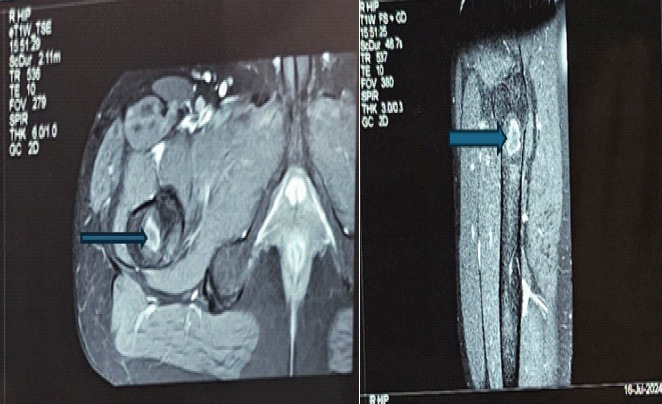

Case report: A 31-year-old apparently normal Indian male presented with pain and swelling of his right proximal femur for 8 months without any history of trauma. He also reported a similar swelling in his chest wall with allergic respiratory symptoms for 8 years. Laboratory analysis revealed mild elevation in inflammatory markers. Magnetic resonance imaging of the pelvis revealed osteolytic lesions in the right proximal femur and pubic bone with soft tissue collections, and computed tomography scan of the chest showed an osteolytic lesion in the right 9th rib with an overlying soft tissue collection and a subpleural cavitary nodule in the left lower lobe posterior basal segment. Although initially treated as a case of clinically diagnosed tuberculosis, the patient did not get any relief with antitubercular therapy. Fine needle aspiration cytology and fungal culture identified Cryptococcus neoformans from both lesions and from the blood culture. The patient responded well to antifungal treatment and is currently symptom free.